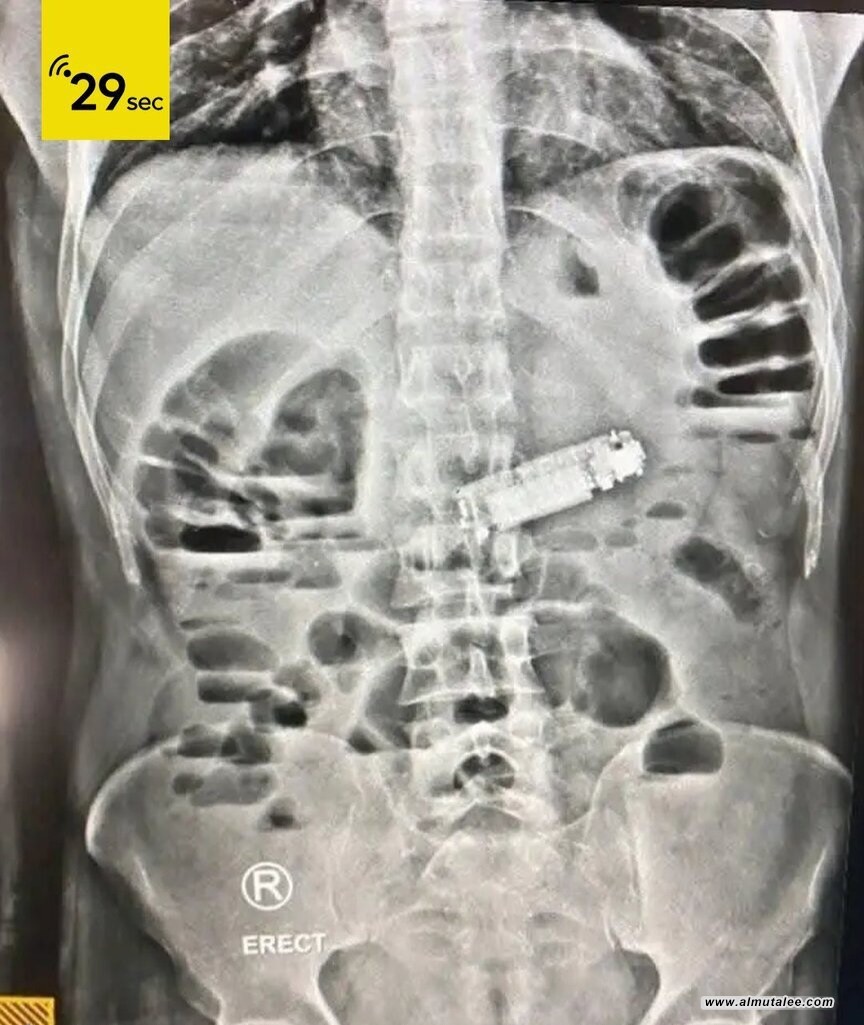

وبعد إجراء الفحوصات الطبية والأشعة اللازمة، تم الكشف عن وجود جسم غريب يسبب انسدادا في فتحة البواب في المعدة، وهو الهاتف المحمول.